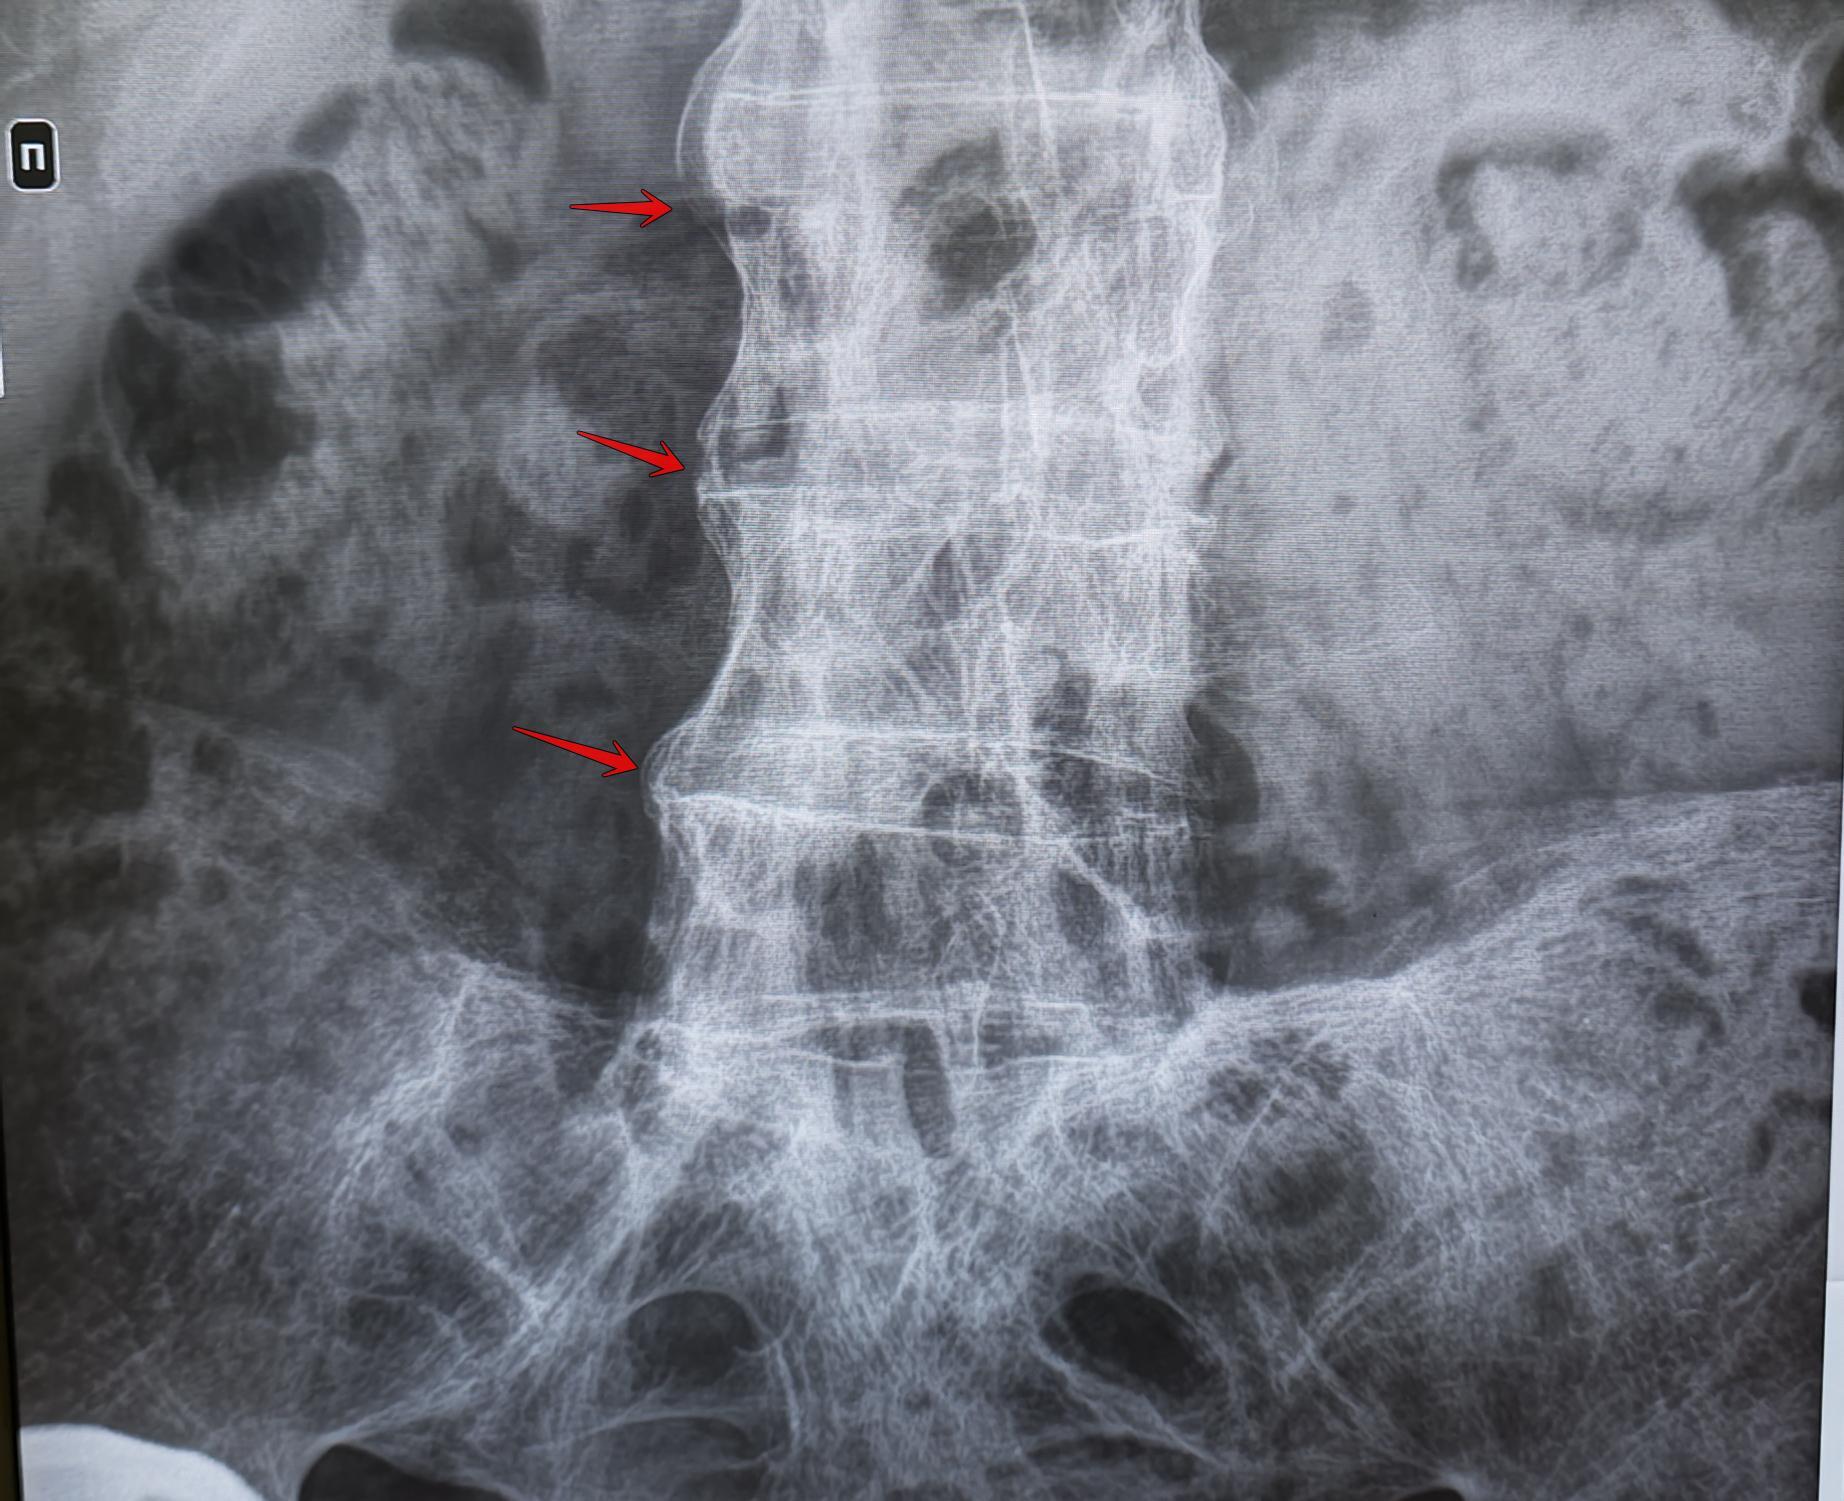

На Р-граммах поясничного отдела позвоночника в 2х проекциях: структура костной ткани позвонков разряжена, высота тел L3,L5 неравномерно снижена в пределах 20% в передних и средних отделах, неравномерное умеренное сужение межпозвонковых рентгенологических пространств, субхондральный склероз замыкательных пластинок, краевые остеофиты. Оссификация передней продольной связки позвоночника на всем протяжении-синдесмофиты.

Заключение: Анкилозирующий спондилит поясничного отдела позвоночника (б.Бехтерева).Дегенеративно-дистрофические изменения поясничного отдела позвоночника. Остеопороз.